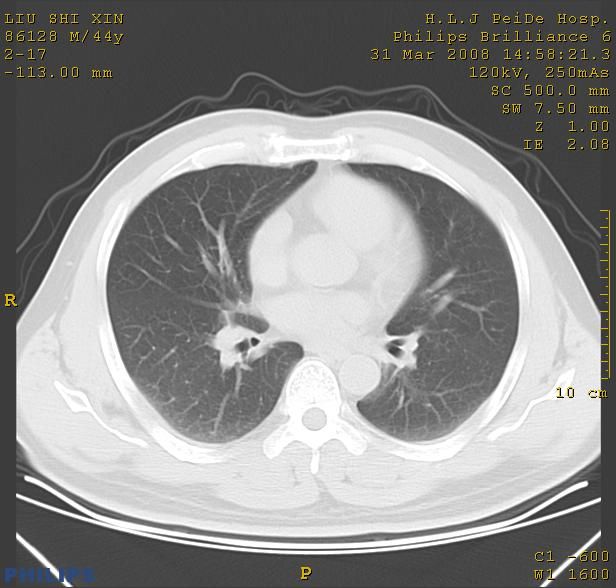

标题: CT13096:请分析胸膜下结节的影像基础是什么 有病理结果 [打印本页]

标题: CT13096:请分析胸膜下结节的影像基础是什么 有病理结果

瘢痕挛缩,胸膜牵拉,血管纠集扭曲,上叶前段支气管显示欠清,周围散在斑片影,以纵隔旁肺癌可能性大。请穿刺检查。

中心型肺癌并阻塞性肺炎及肺内转移

中心型肺癌并阻塞性肺炎、两肺及胸膜多发转移。

结节灶与血管末梢相通象转移灶;小三角状尖部有纤维索是胸膜拉扯征;纵隔旁大片实性影有点状钙化;周围有名显纤维瘢痕征可考虑瘢痕癌

本病例有病理结果是,鳞状上皮癌,胸膜下结节影病现诊断的肿大淋巴结,谢谢大家分析,请问胸膜下结节是肿大淋巴结怎么解释